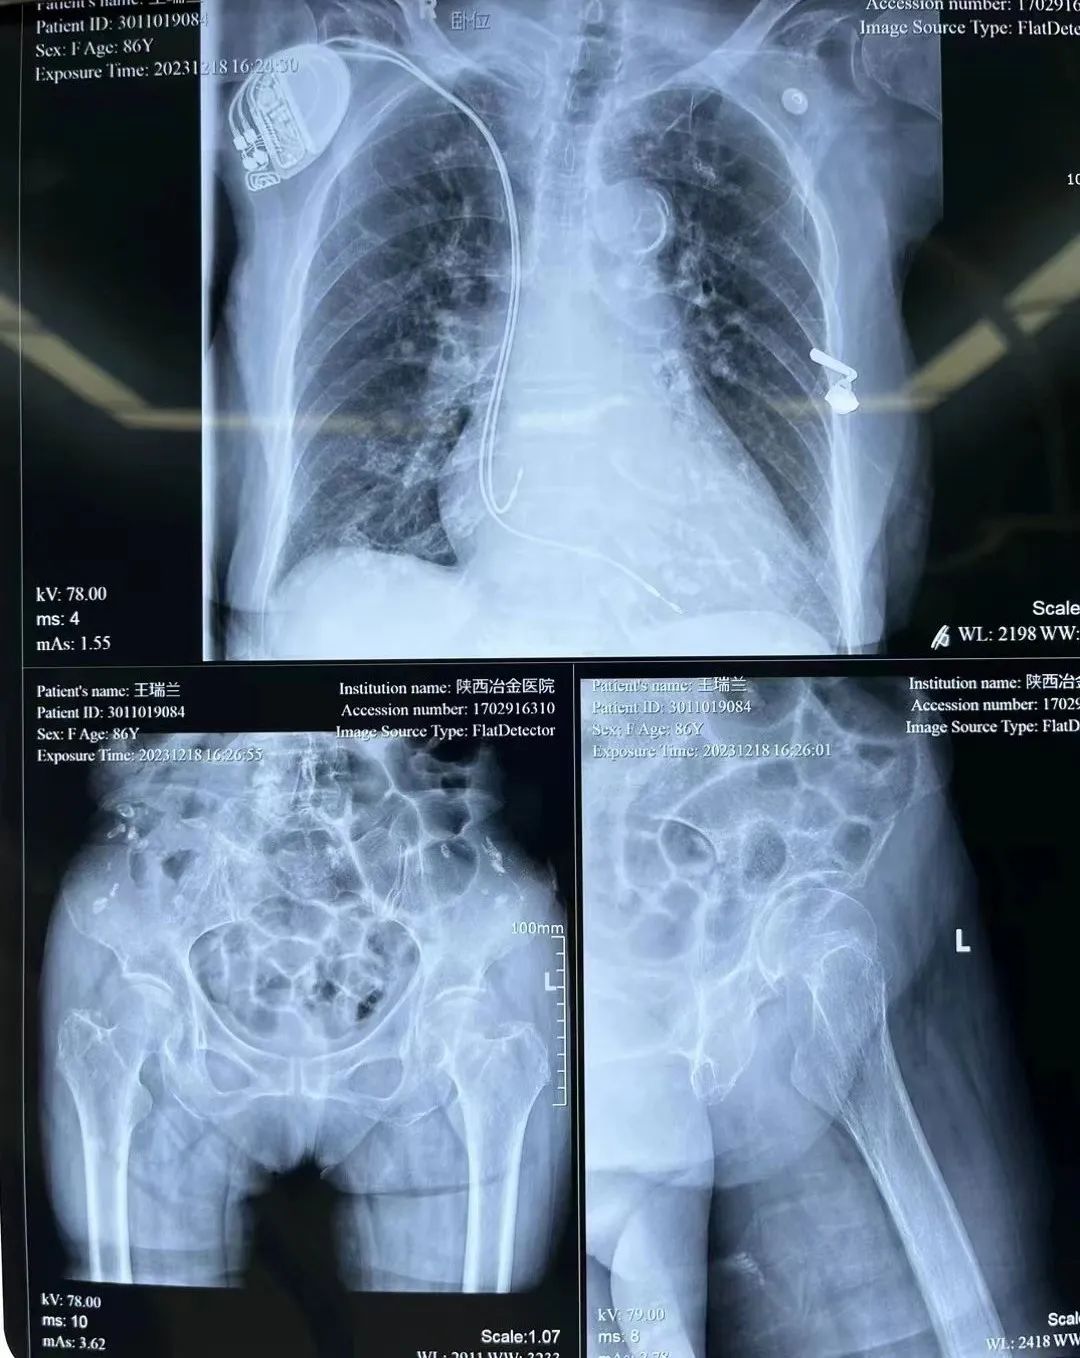

86岁的王奶奶(化名),在家中不慎跌倒,左髋部着地,导致左股骨颈骨折。因有严重的心脏病还装有心脏起搏器,合并多种基础病,辗转多家医院未能手术,经朋友介绍王奶奶在家属的陪伴下来到陕西冶金医院骨科就诊。

▲ 图:王奶奶的X光片